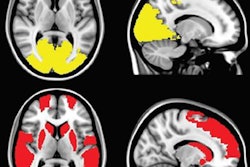

Using focused ultrasound, clinicians can interrupt faulty brain circuits or destroy unwanted tissue without the need to drill or cut into the skull. MRI allows the researchers to monitor the location and intensity of the procedure in real-time.